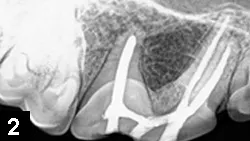

Client Expectations  If clients are not interested in preserving the tooth, extraction is best; if they do wish to preserve the tooth, vital pulp therapy, standard root canal therapy (Figure 2), or surgical root canal therapy can be considered. In more complicated situations, and to include all options, consultation with a board-certified veterinary dentist may be helpful.

Figure 2. A right maxillary 4th premolar tooth (ie, #108) following standard root canal therapy (complete pulpectomy and pulp canal obturation)